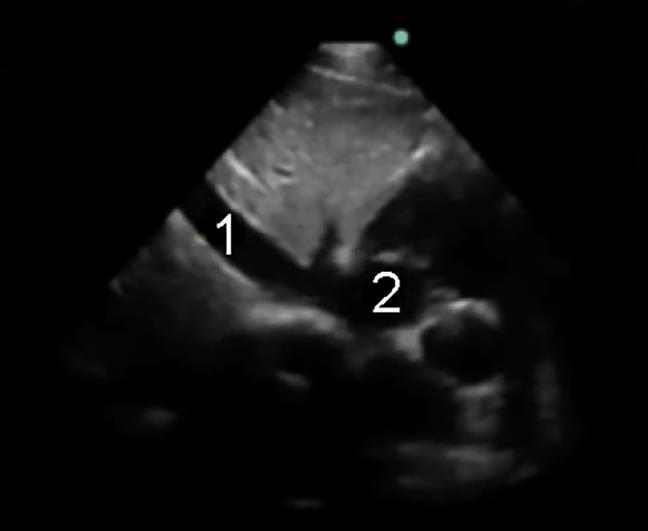

Inferior Vena Cava (IVC) Evaluation Image

Inferior Vena Cava (IVC)

Right Atrium (RA)